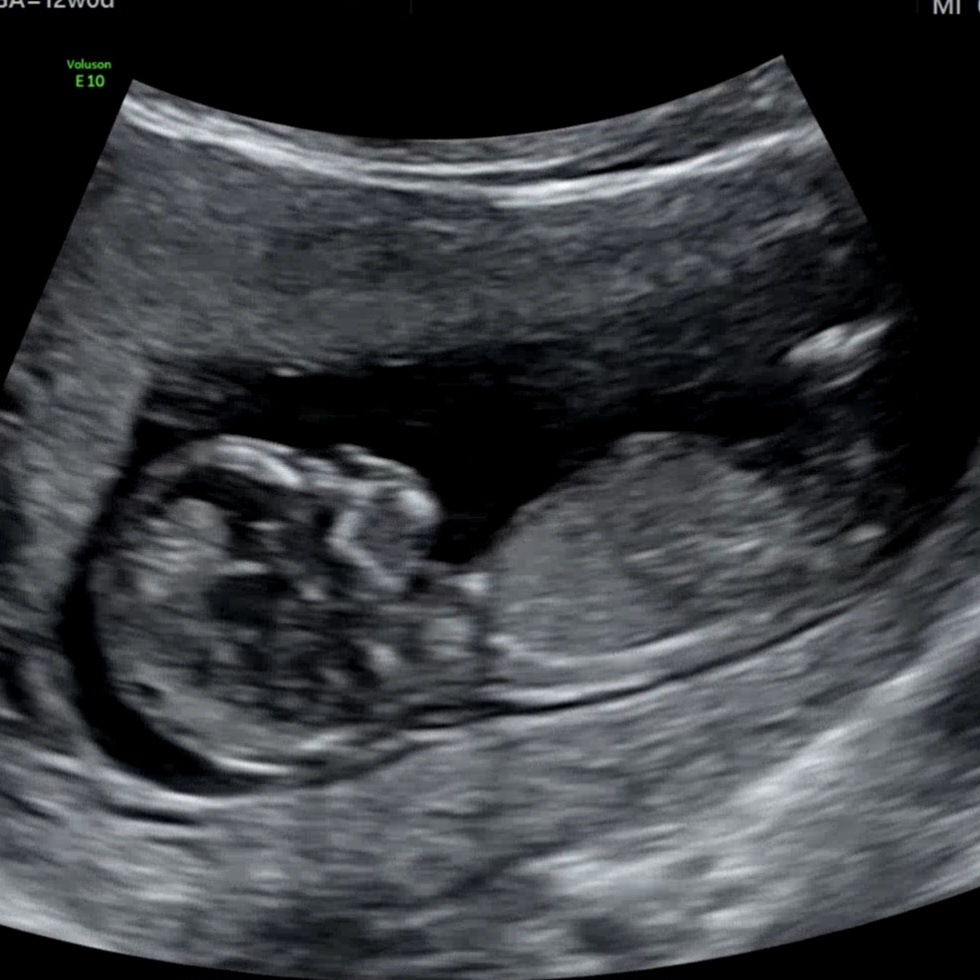

다리사이에 있다가 없다가....?

12주 기형아 검사 진행했어요. 초음파상으로는 잘 크고 있다니 정말 다행이에요 항상 건강만 했으면 하는 마음이지만 성별이 궁금한건 어쩔 수 없나봐요 ㅎㅎㅎ 니프티를 안하니, 한달 뒤에나 정확하게 알수 있을텐데.... 🥲 혹시 사진속 다리 사이에 저것이.. 🌶일까요...?